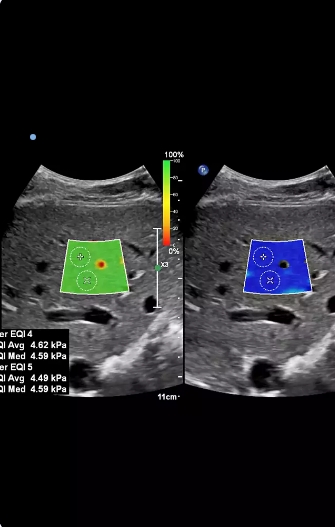

Shearwave Liver Elastography/ Fibroscan

Non-invasive assessment of liver health using advanced ultrasound technology.